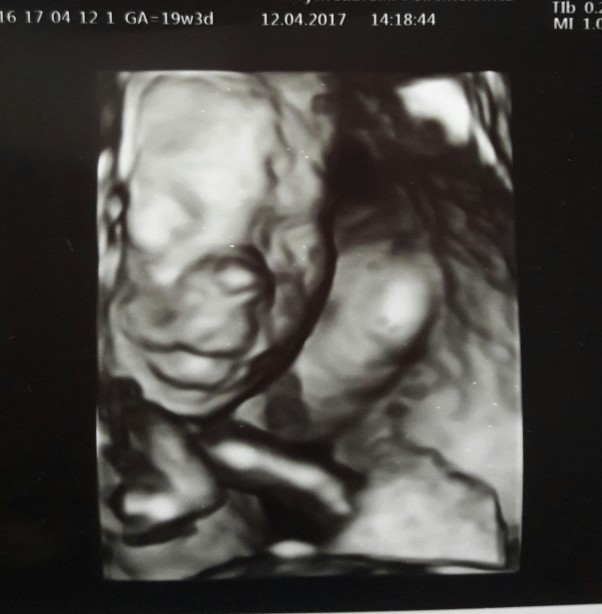

Byłam dzisiaj na usg, lekarz robił je 40 minut :) dzidziuś rośnie zdrowo, waży już 280g i na pewno będzie chłopiec :) Całe badanie się kręcił i kopał. Dawid i Julka też przyszli pod koniec badania i widzieli małego na monitorze a także słuchalismy bicia serduszka :)